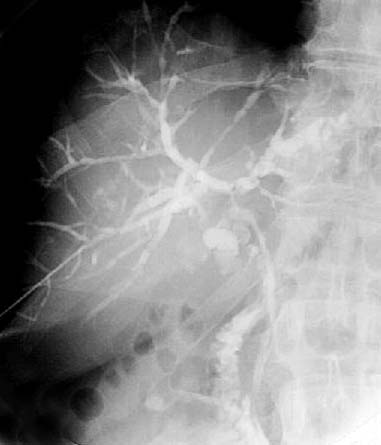

図 ERCPによる beaded appearance

若年性では胆管壁に玉葱状の線維化と炎症性細胞浸潤がみられるのに対し,高齢者では肝外胆管に病変が多く,胆管周囲にはリンパ球や形質細胞の浸潤がみられ,胆管上皮は比較的保たれているという違いがみられます.